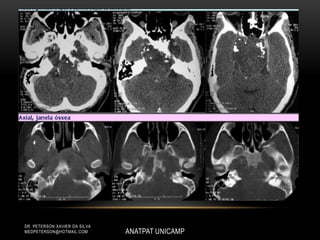

• Lesão lítica, destrutiva, podendo apresentar

esclerose marginal.

• Componente de tecido de partes moles, geralmente

mais extenso que o acometimento ósseo, por conta

de áreas de necrose cística ou hemorragia.

• Calcificação intratumoral.

• Captação de contraste moderada a intensa.

• Lesão lítica,destrutiva, podendo apresentar esclerose marginal. • Componente de tecido de partes moles, geralmente mais extenso que o acometimento ósseo, por conta de áreas de necrose cística ou hemorragia. • Calcificação intratumoral. • Captação de contraste moderada a intensa. ANATPAT UNICAMP DR. PETERSON XAVIER DA SILVA MEDPETERSON@HOTMAIL.COM CORDOMA DE CLIVUS

• #6 • Lesão lítica, destrutiva, podendo apresentar esclerose marginal. (CLIVUS E COMPOSTO DO BASOESFENOIDE E DO BASOCCOPITO) • Componente de tecido de partes moles, geralmente mais extenso que o acometimento ósseo, por conta de áreas de necrose cística ou hemorragia. • Calcificação intratumoral. • Captação de contraste moderada a intensa.

• #7 • Lesão lítica, destrutiva, podendo apresentar esclerose marginal. • Componente de tecido de partes moles, geralmente mais extenso que o acometimento ósseo, por conta de áreas de necrose cística ou hemorragia. • Calcificação intratumoral. • Captação de contraste moderada a intensa.

• #8 • Lesão lítica, destrutiva, podendo apresentar esclerose marginal. • Componente de tecido de partes moles, geralmente mais extenso que o acometimento ósseo, por conta de áreas de necrose cística ou hemorragia. • Calcificação intratumoral. • Captação de contraste moderada a intensa.